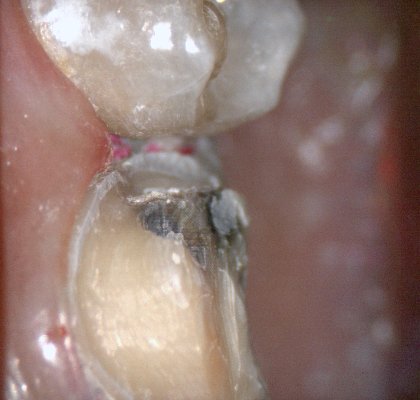

The following pictures depict the sequence of burs we recommend that you use to finish a preparation quickly. While patient is getting numb, take a quick look at the clearance you will need to reach proper material thickness. Once the quadrant is isolated with isolite and optragate, take an occlusal router bur and create a trough to gain the proper depth. Follow that with a flat disk, and you can quickly reduce the occlusal height.

A shoulder bur of .8 mm thickness can help you reduce the interproximal areas as well as the buccal and lingual margin lines. Before finishing the prep, place hemostatic agent like expasyl in the sulcus and place retraction cord. while it is setting, check your reduction. If you need more space, now is the time to reduce some more.

Once you have adequate clearance, retraction, and hemostatis, you can readily image and find your margins in the CAD software